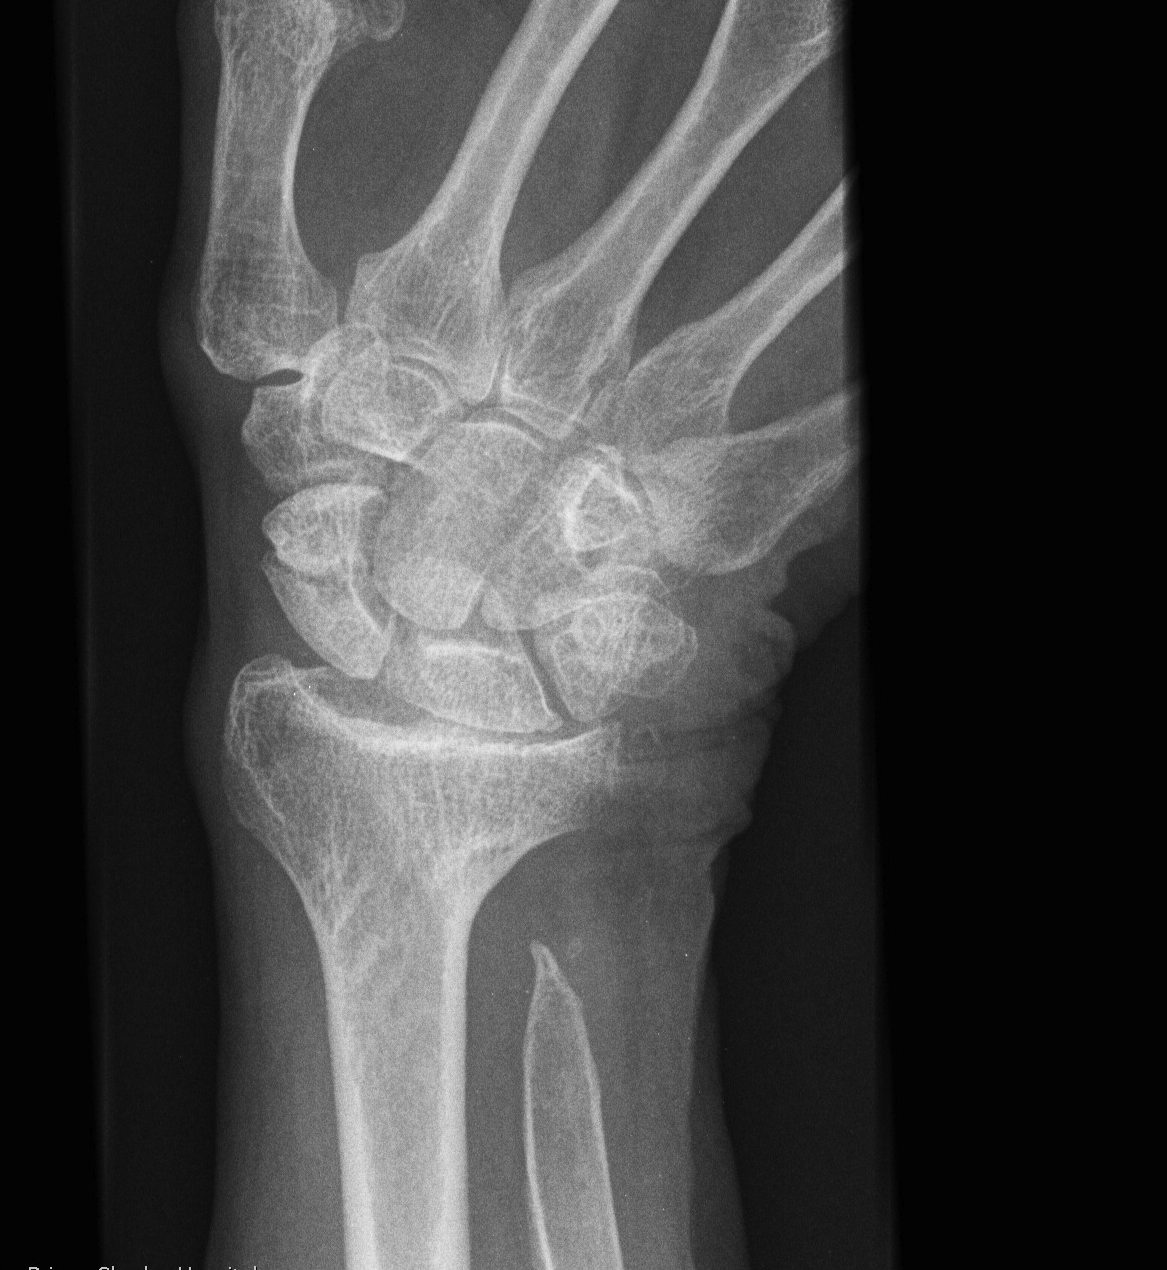

X-ray

Volar-ulna tilt of the distal radius with dorsal subluxation of ulna / distal radius triangular shape

Proximal carpal row becomes wedge shaped

- lunate "falls into" the radio-ulna gap

DRUJ widened

Chevron

- proximal carpal row distorted / V-shape

- lunate in apex between radius and ulna